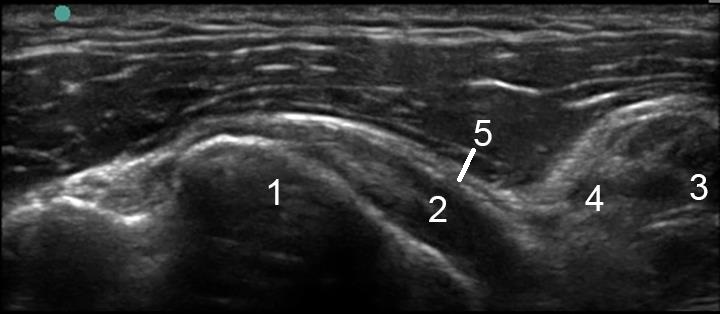

1. Lesser Tuberosity

2. Subscapularis Tendon

3. Coracobrachialis

4. Short Head of the Biceps Tendon

5. Subacromial Subdeltoid Bursa